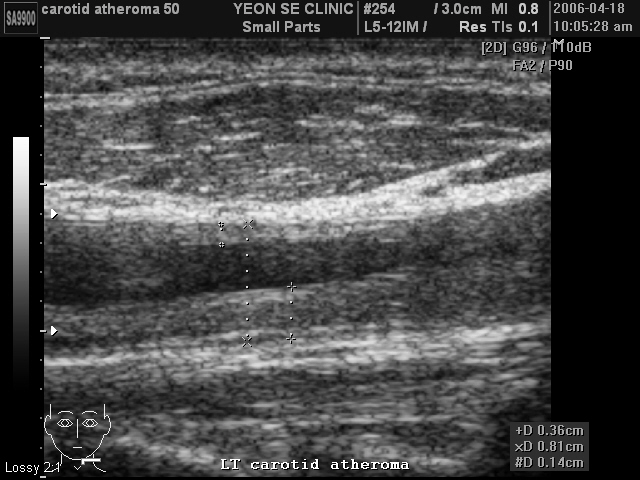

Ultrasonographic data of our patients

Carotid at...